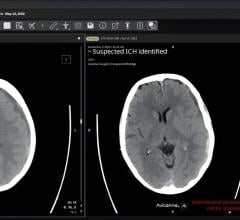

Sept. 25, 2025 — RamSoft Inc., a provider of cloud-based RIS/PACS radiology solutions, has announced a new ...